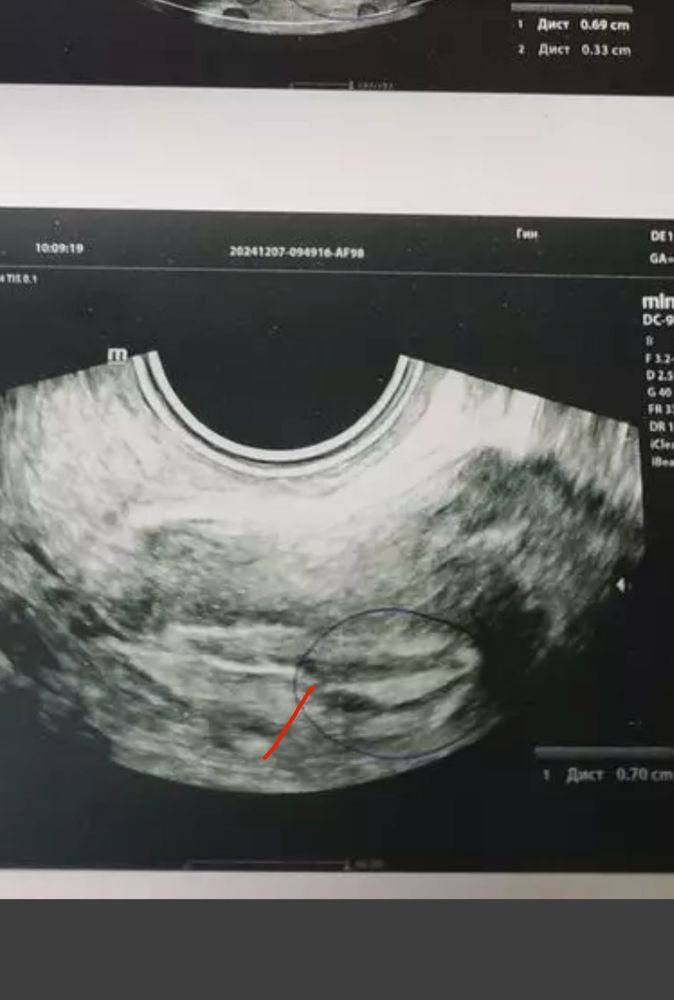

Тут прерывистая линия. Поэтому подумали на полип.

Если нет жалоб, то можно подождать . полипы до 1см самостоятельно могут оторваться и выйти с месячными… либо это не полип вовсе, а складка эндометрия.